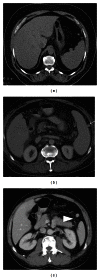

Spleen can have a wide range of anomalies including its shape, location, number, and size. Although most of these anomalies are congenital, there are also acquired types. Congenital anomalies affecting the shape of spleen are lobulations, notches, and clefts; the fusion and location anomalies of spleen are accessory spleen, splenopancreatic fusion, and wandering spleen; polysplenia can be associated with a syndrome. Splenosis and small spleen are acquired anomalies which are caused by trauma and sickle cell disease, respectively. These anomalies can be detected easily by using different imaging modalities including ultrasonography, computed tomography, magnetic resonance imaging, and also Tc-99m scintigraphy. In this pictorial essay, we review the imaging findings of these anomalies which can cause diagnostic pitfalls and be interpreted as pathologic processes.